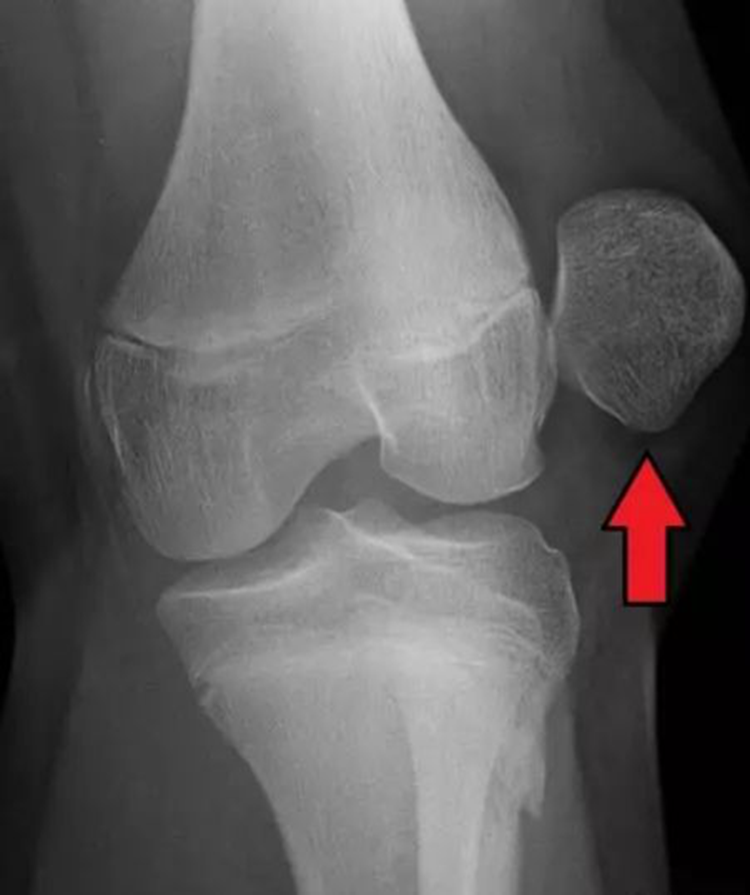

近日,我院疼痛科顺利完成一例“关节镜下左侧膝关节探查游离体取出术+C臂机下左侧髌股韧带重建术”,该患者5年前曾有左侧膝关节外伤史,伤后左侧膝关节时感不适。2月前患者左侧膝关节再次受伤,伤后左侧膝关节肿痛明显,症状愈发加重,遂到我院求诊。入院行相关检查后诊断为左髌骨脱位、髌股韧带断裂。疼痛科主任陈永富根据患者病情,为患者行关节镜联合C臂精准定位行膝关节微创治疗,术中仅在患者膝关节前方做四个约1cm的小切口,就在关节镜下一次性完成精确的病变切除或修复治疗。术后第一天患者关节疼痛感明显减轻,能正常行走,对手术疗效非常满意。此次手术的成功,也标志着我院疼痛微创手术跃上了一个新的台阶。 (投稿/疼痛科 陈永富)